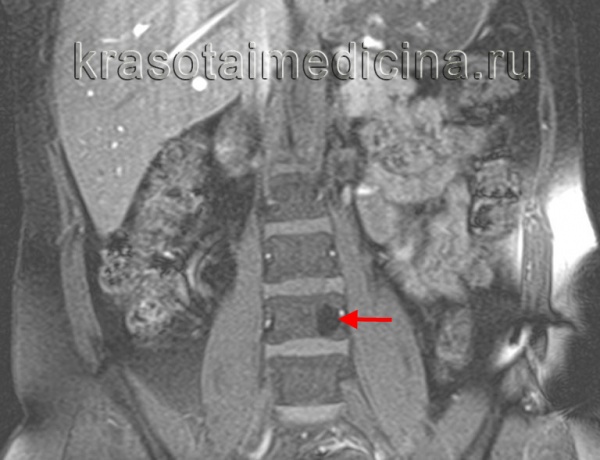

(Слева) Аксиальный срез, Т2-ВИ поясничного позвонка: четко ограниченное гиперинтенсивное образование. Мелкие гипоинтенсивные вкрапления соответствуют утолщенным костным трабекулам, которые хорошо видны на КТ.

(Справа) Сагиттальный срез, Т1-ВИ: бедная жировой тканью гемангиома L5 позвонка, характеризующаяся диффузной гипоинтенсивностью сигнала тела позвонка Также визуализируется вентральный эпидуральный компонент, сдавливающий дуральный мешок, характеризующийся смешанной интенсивностью сигнала жировой ткани и мягких тканей, представляющий собой экстраоссальный компонент гемангиомы.